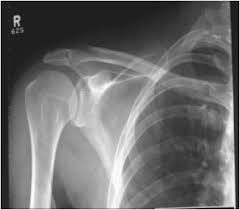

What is Radiography, wherein the electromagnetic radiation passes through a part of the body to produce an image of internal structures in the film. X-rays are a great way to show dense areas of the body such as bone or a tumor,

What is Radiography, allowing only a few rays to pass. Dense areas appear as white areas on the film. Doctors use X-rays to examine the chest, skull and spine and see which one can fracture the bone. Even the body is filled with liquid, gas or air, such as arteries, colon or bladder can be seen with X-rays, if the instruments are the first walled city with a special liquid dye, called the contrast.